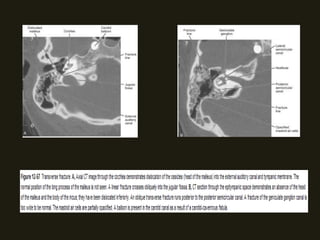

FRATURAS

LONGITUDINAIS

• Ocorrem no eixo longitudinal da pirâmide petrosa; podem

estender-se para porção escamosa e para a cavidade

timpânica;

• Cursam com perda auditiva, paralisia facial;

TRANSVERSAIS

• 20% casos;

• Atravessam o osso temporal de posterior para anterior;

• Causam disfunção labiríntica e “ouvido morto” se o traço de

fratura atravessar o vestíbulo, canais semicirculares ou a

cóclea; Pode paralisia facial;